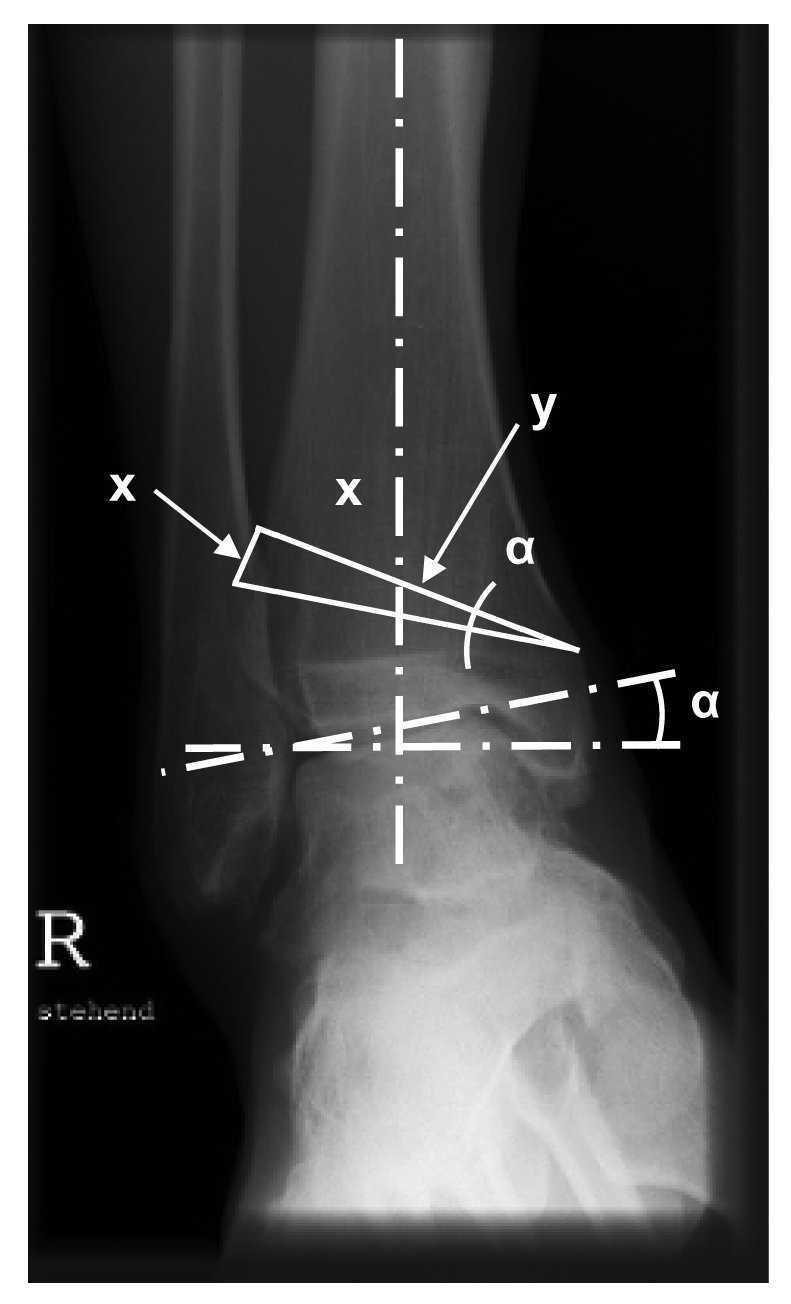

Figura 1. Planificación de la osteotomía. La siguiente operación permite calcular aproximadamente la altura de la base de la cuña que debe extraerse de la tibia: x = y x tan a. En la osteotomía, por tanto, se realizará probablemente una corrección de 1º para una resección de 1 mm (menor en correcciones más pequeñas).

Figura 2. CORA (centro de rotación y angulación): en las deformidades postraumáticas, deberá planificarse la osteotomía a la altura de la desviación del eje; de lo contrario se produciría una traslación de la porción distal con el correspondiente desplazamiento del eje mecánico de la articulación.